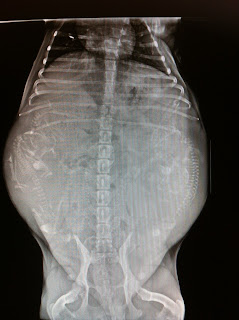

Snart e det dags för Nanna :) MD Billie Jean

Ser ni hur många bebisar där är?